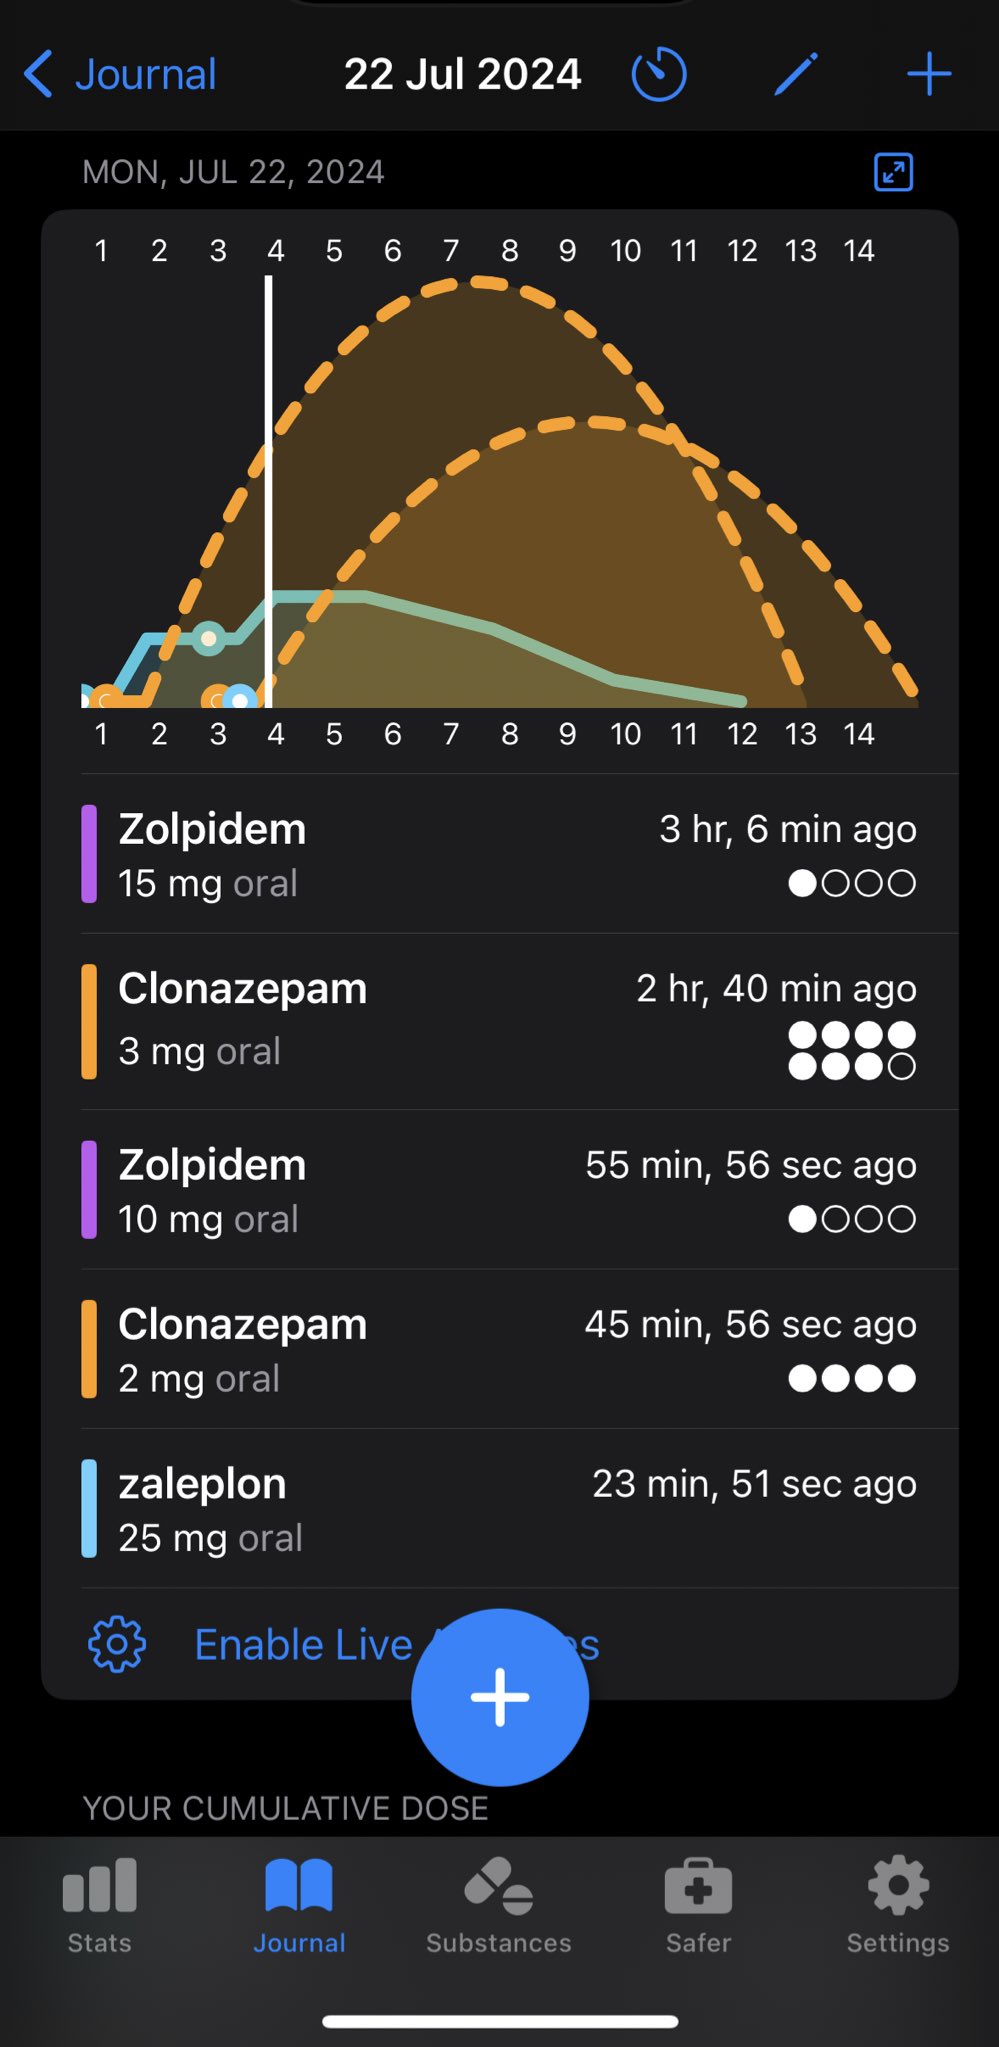

炽烈已极 @AnIncandescence@whitenightX3 journal

2026-01-28 12:16:34 UTC